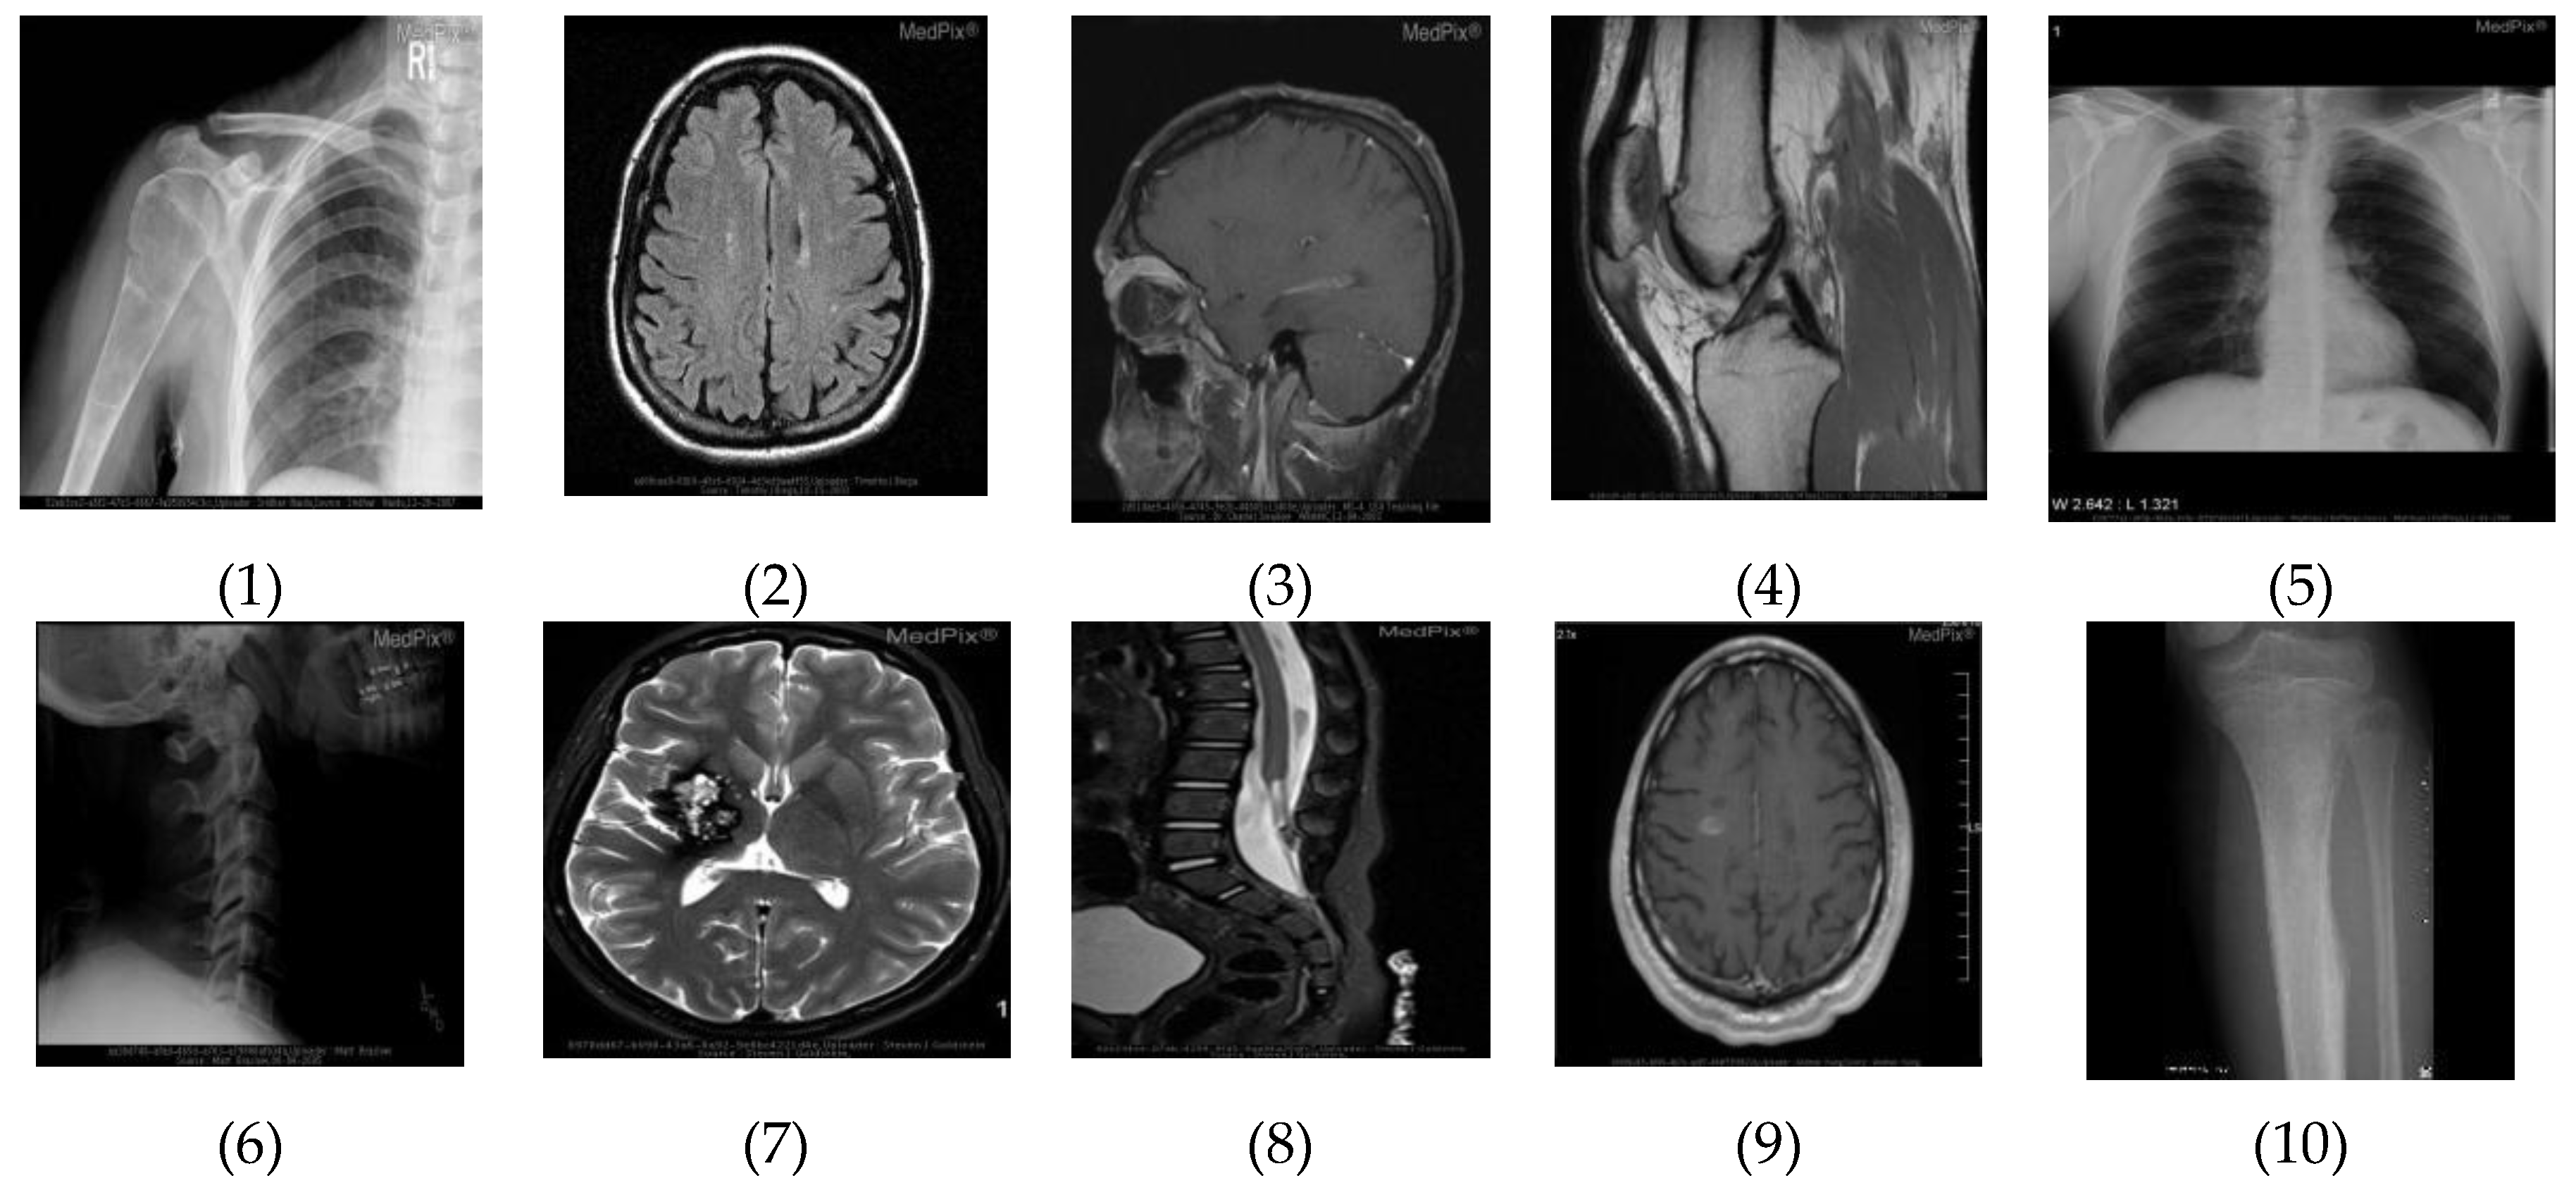

We present experimental results of our method on various radiographic images. The parameters of the proposed algorithms were fixed to obtain overall optimal results in terms of image metrics. We analyze the results on 10 radiographic images taken from MedPix database. MedPix is a free online medical image database with over 53,000 indexed and curated images from over 13,000 patients. As shown in Figure 2, we number these images from 1 to 10 (according to the order from left-to-right and top-to-bottom.

Figure 2.

Set of testing images (referred to as 1 to 10, from left-to-right and top-to-bottom).

Computational results of the analysis of image in Figure 2(1) show that there are 48,221 pixels with same color in the image. These pixels are shown in Figure 3(1) with white region. Similarly, Figure 2(2) has 42,997 pixels having same color. Figure 2(3) has 37,863 pixels, Figure 2(4) has 19,256 pixels, Figure 2(5) has 134,993 pixels, Figure 2(6) has 83,749 pixels, Figure 2(7) has 17,890 pixels, Figure 2(8) has 24,892 pixels, Figure 2(9) has 74,785 pixels, and Figure 2(10) has 11,786 pixels with the same color.